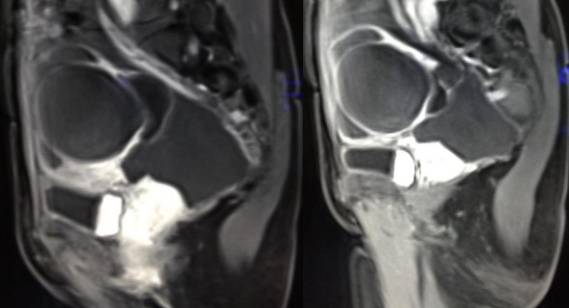

MR检查:

病理结果:黄体血肿

黄体血肿为正常排卵过程中,卵泡层破裂,引起出血,较多的血液潴留在卵泡或黄体腔内形成血肿。

正常黄体直径为15mm左右,以后转变为白体,并在下一个周期的卵泡期自然消退。若黄体内出血量较多,则形成黄体血肿,或称黄体内出血,出血性黄体。黄体血肿多为单侧,一般直径为40mm,偶可达100mm,黄体血肿被吸收后可导致黄体囊肿,较大的血肿破裂时可出现腹腔内出血,剧烈腹痛、少量阴道流血和腹膜刺激征,不易与宫外孕区别。

根据时间不同MR信号也有所不同,TIWI脂肪抑制序列可以鉴别脂肪和出血。